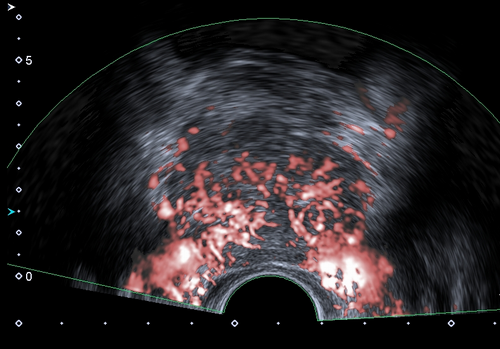

自临床使用以来,检查医生都反应二维图像很清晰,特别是一些新增功能,更受欢迎。1.彩超血流技术除常规CDFI、高级动态血流技术外,还具备超微细血流技术,能检测极低速血流(流速0.1-0.4cm/s),而微细低速血流广泛存在于各类疾病病灶的滋养血流、新生血流,能快速、便捷的帮助超声医生对疾病的准确诊断和鉴别诊断。2.声衰减成像功能,可对肝脏组织的衰减系数进行测量及可视化显示,可以对脂肪肝作出量化诊断,是诊断脂肪肝的有效定量工具。早期发现和量化评估肝脂肪变性,利于及时处理,防止病程进展。3.双平面探头(凸阵+线阵),为前列腺穿刺、肛周脓肿、阴道尿道、盆底功能障碍等疾病的诊断治疗提供不可替代的优势。凸、线双平面探头在前列腺、肛周穿刺活检中,实时快捷观察冠状面、矢状面,确定穿刺针路径、位置,提高穿刺活检成功率。4.浅表微小钙化增强显示技术,显著提升0.1-0.2mm微钙化点的检测识别能力。可以与原始图像实时双幅对比显示,可应用在乳腺、甲状腺等腺体组织恶性肿瘤的早期筛查。5.术中探头,配置穿刺引导架、能提高肝、肾等腹腔脏器的穿刺准确率。